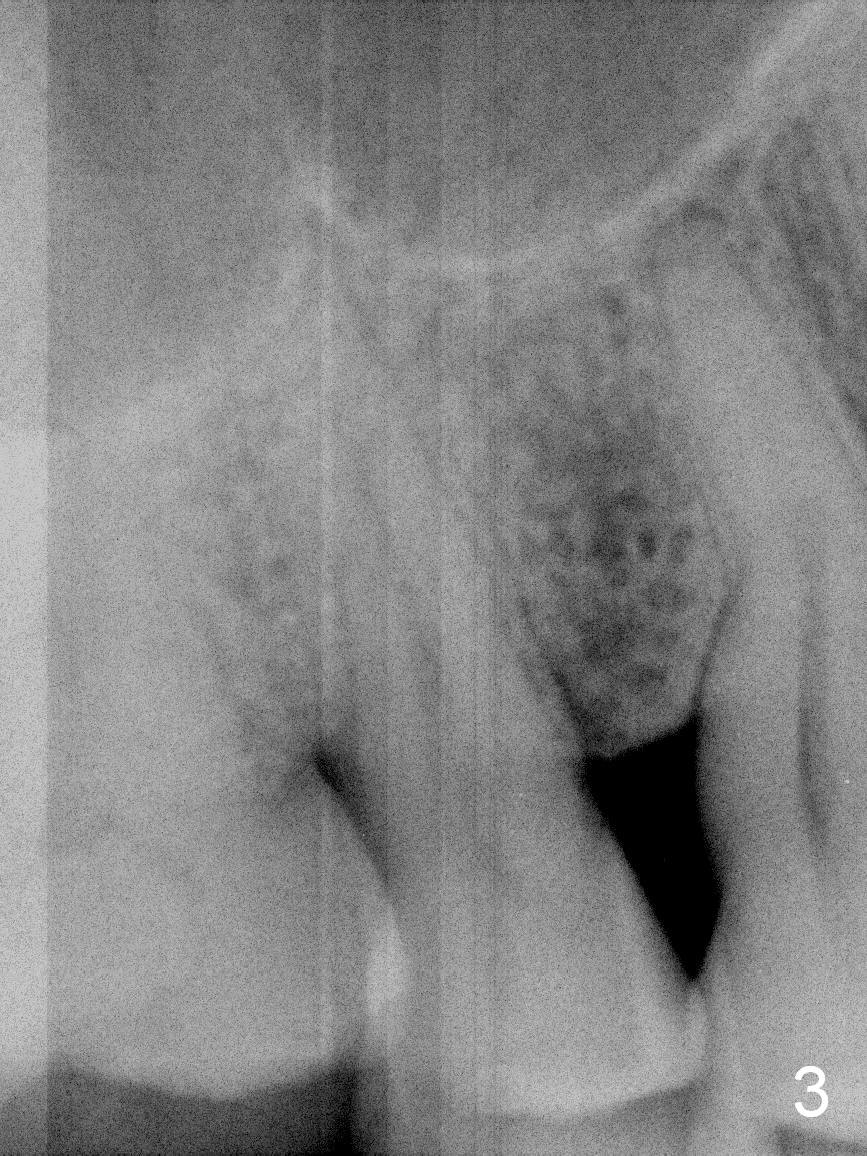

A 61-year-old man (WJ) cracked the tooth #31 after RCT. Four years after #31 extraction, the tooth #4 cracks by itself. The apex of the tooth appears to protrude into the sinus and is closely associated with the sinus septum (triangle: Fig.2,3). An implant will reach the top of the socket for stability (Fig.4 black area). The abutment is expected to be 4.8x4(3) (SM) or 4.5x4(3) (UF) mm. Metronidazole will be used for disinfection of the socket. On returning, he requests #31 implant.